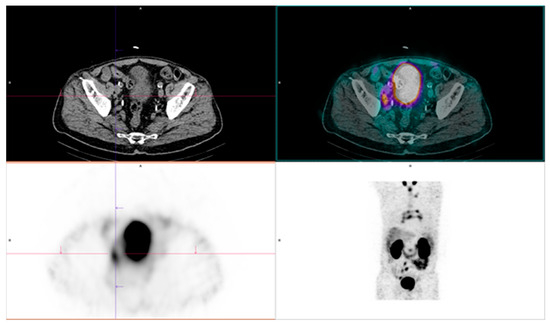

2.4. PSMA-Targeting Radiopharmaceutical PET/CT